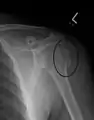

A spiral fracture of the distal one-third of the humerus shaft

A displaced supracondylar fracture in a child